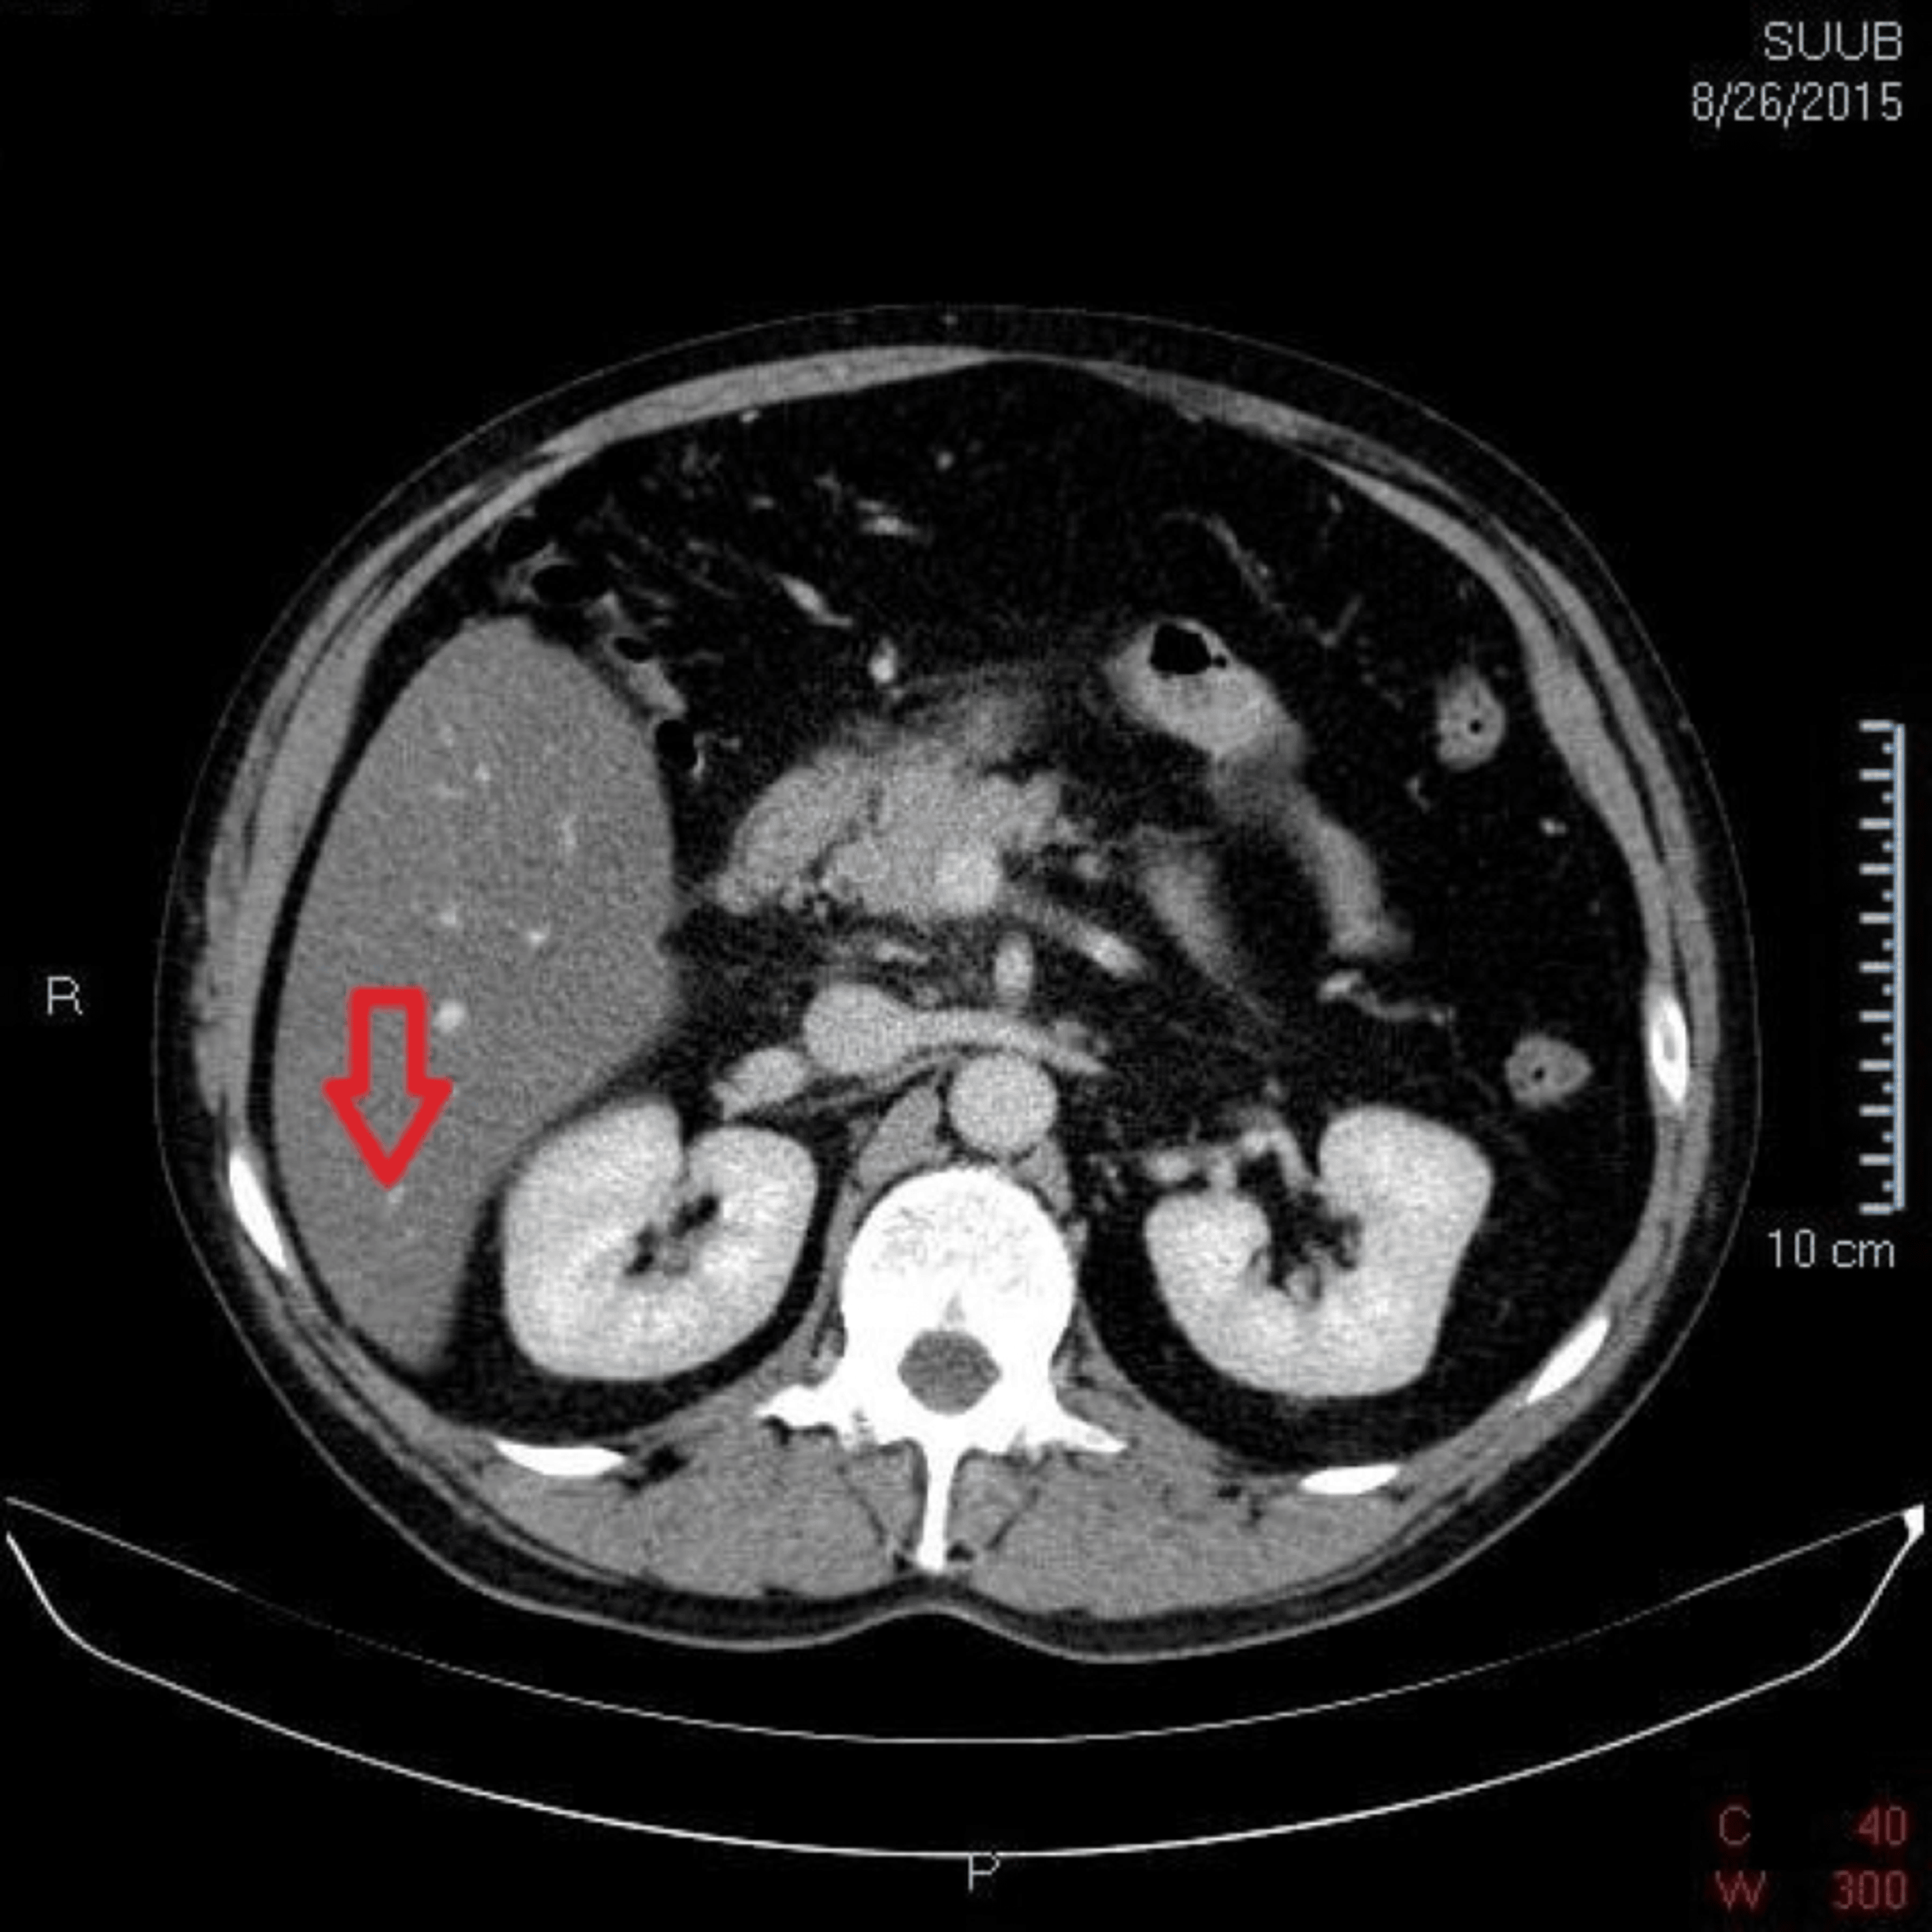

Riedel lobe Image

Riedel lobe Image What Is Riedel Lobe riedel’s lobe is a rare anatomical variant of the liver with a downward projection of the anterior right. riedel's lobe is a normal variant form of right liver lobe rarely found. Here we report a case of 38 years old female with an incidental. the differential diagnoses include hepatomegaly and accessory liver lobes. Although most accessory lobes. What Is Riedel Lobe.

Riedel lobe Image What Is Riedel Lobe riedel’s lobe is a rare anatomical variant of the liver with a downward projection of the anterior right. Although most accessory lobes are. the differential diagnoses include hepatomegaly and accessory liver lobes. Here we report a case of 38 years old female with an incidental. riedel's lobe is a normal variant form of right liver lobe rarely. What Is Riedel Lobe.

Riedel lobe Image What Is Riedel Lobe Here we report a case of 38 years old female with an incidental. riedel’s lobe is a rare anatomical variant of the liver with a downward projection of the anterior right. Although most accessory lobes are. riedel's lobe is a normal variant form of right liver lobe rarely found. the differential diagnoses include hepatomegaly and accessory liver. What Is Riedel Lobe.